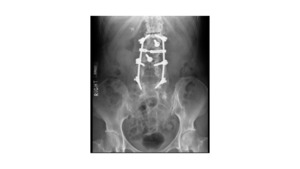

A 63-year-old female presented with recurrent THA instability - verbal consent was obtained for this report. She underwent L2-S1 posterior stabilization with L2-L3 anterior lumbar interbody fusion in May 2002 (Figure 1) and an uncomplicated right THA in April 2007. (Figures 2a-b) Five years following primary THA (July 2011), the patient sustained her first THA dislocation, which was treated with a closed reduction. Between 2011 and 2018, the patient had seven repeat episodes of hip instability – in 2012, one was complicated by a peri-prosthetic femur fracture requiring three revisions and reconstruction with a trochanteric claw plate. She was subsequently diagnosed with a prosthetic joint infection (PJI) which required an antibiotic spacer and subsequent re-implantation three months later. (Figures 3a-b) Following treatment of initial instability and femur fracture, the implants included a size 16 standard taper femoral stem and a 50-mm acetabular shell with 32-mm liner.